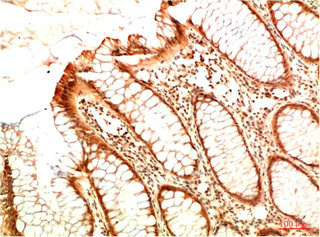

Immunohistochemical analysis of paraffin-embedded Human Colon Carcinoma Tissue using Acetyl P53(K382) Mouse mAb diluted at 1:200.